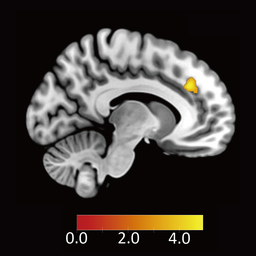

次に、不公平な条件が提示されたときに、この背側前帯状皮質が抑制的に働くと考えられる脳領域、すなわち負の結合度を示す領域を探索したところ、腹外側前頭前野が見つかりました(図3B参照)。さらに、背側前帯状皮質と腹外側前頭前野の結合度から、各参加者が不公平な提案を受け入れる割合(拒否率、図3C参照)と、反応時間(図3D参照)の両方を予測できることが分かりました。一方で、報酬に関わる脳活動からは、このような予測はできませんでした。

(B)Aの脳領域と負の結合度を示す領域(腹外側前頭前野)

(C)背側前帯状皮質と腹外側前頭前野の結合度と不公平な提案の拒否率及び(D)反応時間。結合度が行動選択と反応時間を予測することがわかる。結合度がマイナスの大きな値を取るほど受け入れる率が高く、反応時間も短くなる。